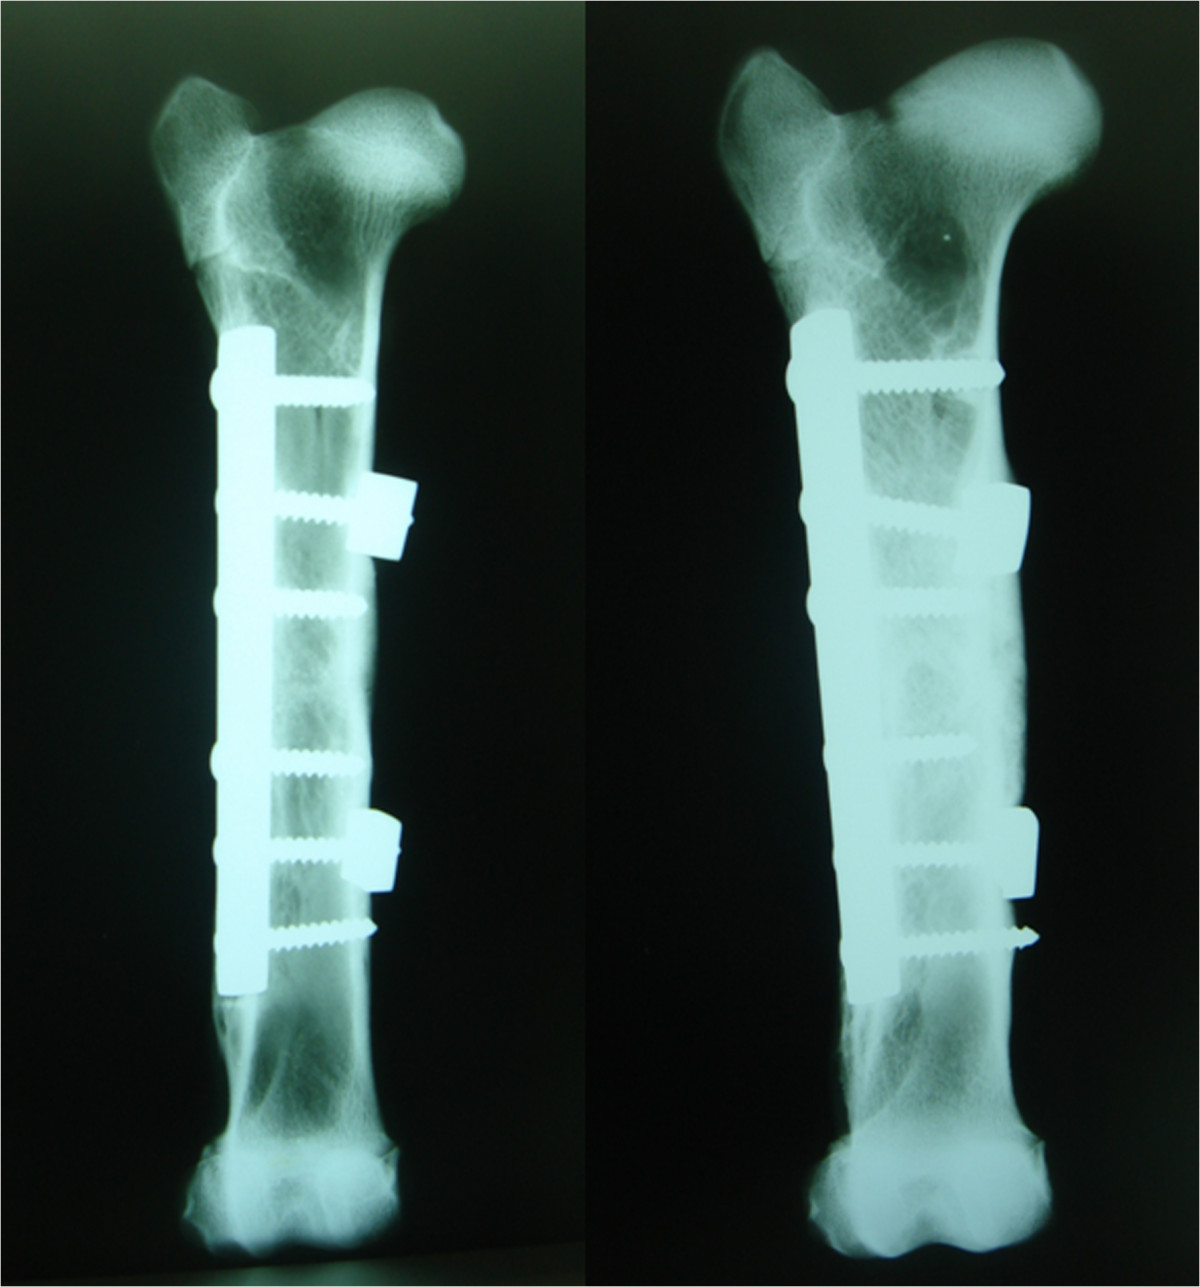

Figure 5.

Two examples of bones operated on with SLE after 16 weeks. Both of them show complete consolidation of the osteotomy and normal alineation.